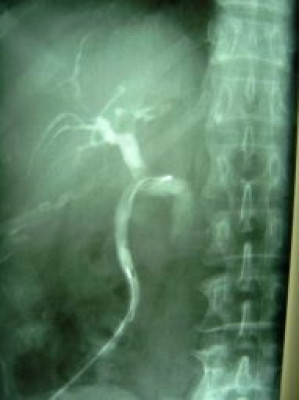

Litotripsia y extracción de cálculo de coledoco residual

Envíado por Dr. Carlos Miguel Zavaleta Consuegra